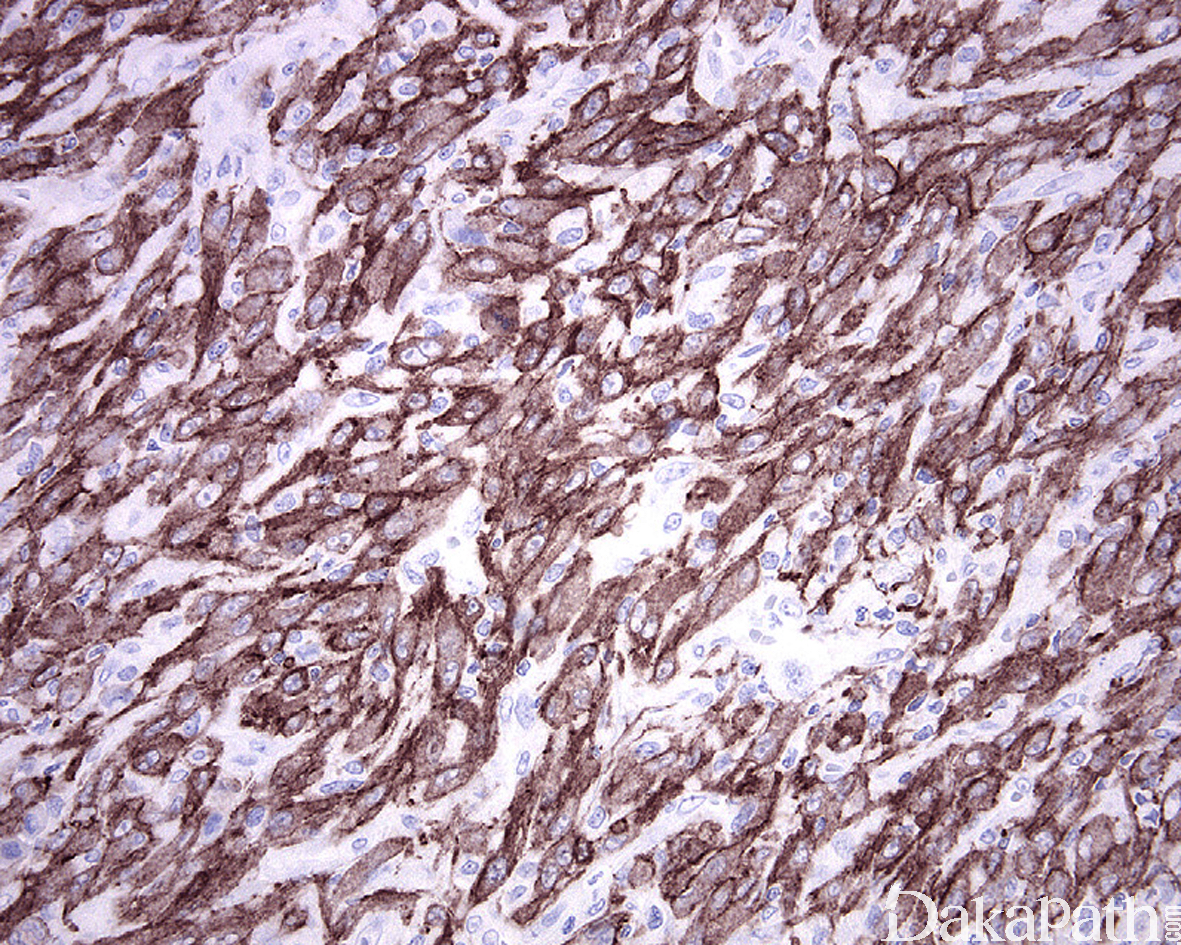

免疫组织化学染色:

半数以上的病例中肿瘤细胞表达 ALK 蛋白,多数病例表达 SMA 和 MSA,部分表达 desmin, 30%左边可表达角蛋白 AE1/3 和 Cam5.2,不表达 S100 蛋白、myogenin、MyoD1. CD117. CD34. CD21. CD35 等标志物。